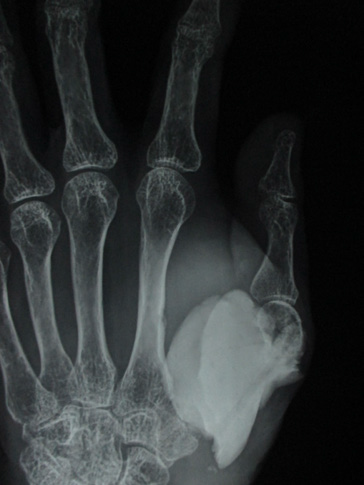

Figure 2 a. Clinical picture on presentation one year after recurrence; b. X-ray at that time showing soft tissue and second MC involvement; c & d. MRI show similar findings but without involvement of major nerve and vessels.

Under tourniquet control and regional anaesthesia through dorsoradial incision the mass along with bone cement was removed, meticulously cleaning of original tumour site was done. Excised tissue was preserve for histopathology (HP). With a separate set of clean instrument the osteolytic area second metacarpal was curetted and the material is preserved in separate jar for HP study. Tricortical bone graft from iliac crest of appropriate size was harvested and placed in position with 4 K-wires. After closure of wound hand and forearm was placed in plaster of Paris slab. Stitches were removed after 2 weeks but cast continued for 2 months and K wires continued for 3 months when graft ends started uniting and partially incorporated (Figure 3). Histopathology reported as GCT without malignancy from both the specimens. 75 % movements of carpometacarpal and metacarpo-phalangeal joints were restricted but interphalangeal joint exhibit 50% motion (Figure 4). Wrist became free. In 1 year 3 months follow up there is no evidence of recurrence or metastasis. Considerable amount of reactive consolidating bone formation around 2nd MC radiologically.